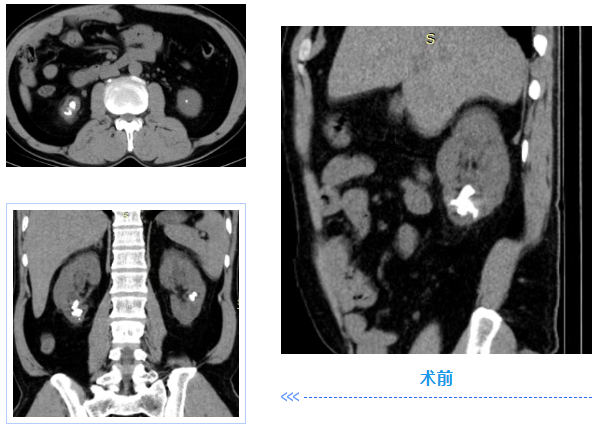

近日,铜仁市万山区人民医院泌尿外科成功为一名肾脏下极复杂多发结石的患者实施了“腹腔镜下肾下极切除术(肾部分切除术)”。

据悉,该患者因结石“盘踞”肾下极,长期受泌尿系结石困扰,辗转多家医院求治,却一直未得到有效治疗,严重影响到生活质量。

“肾下极因解剖位置特殊,是结石高发且难以自然排出的区域。长期梗阻、炎症会导致肾盏颈狭窄、肾局部积水等情况,采用常规的碎石取石术难以从根本上清除结石,且易复发。”泌尿外科主任刘俊介绍道。

面对患者的复杂病情,泌尿外科学科银龄专家罗洪星及刘俊带领团队对患者情况进行充分的术前讨论。考虑到患者肾下极结石集中,对应肾实质已出现萎缩,且肾盏颈存在。结合患者诉求,最终确定采取“腹腔镜下肾下极(即肾部分)切除术”的手术方案。